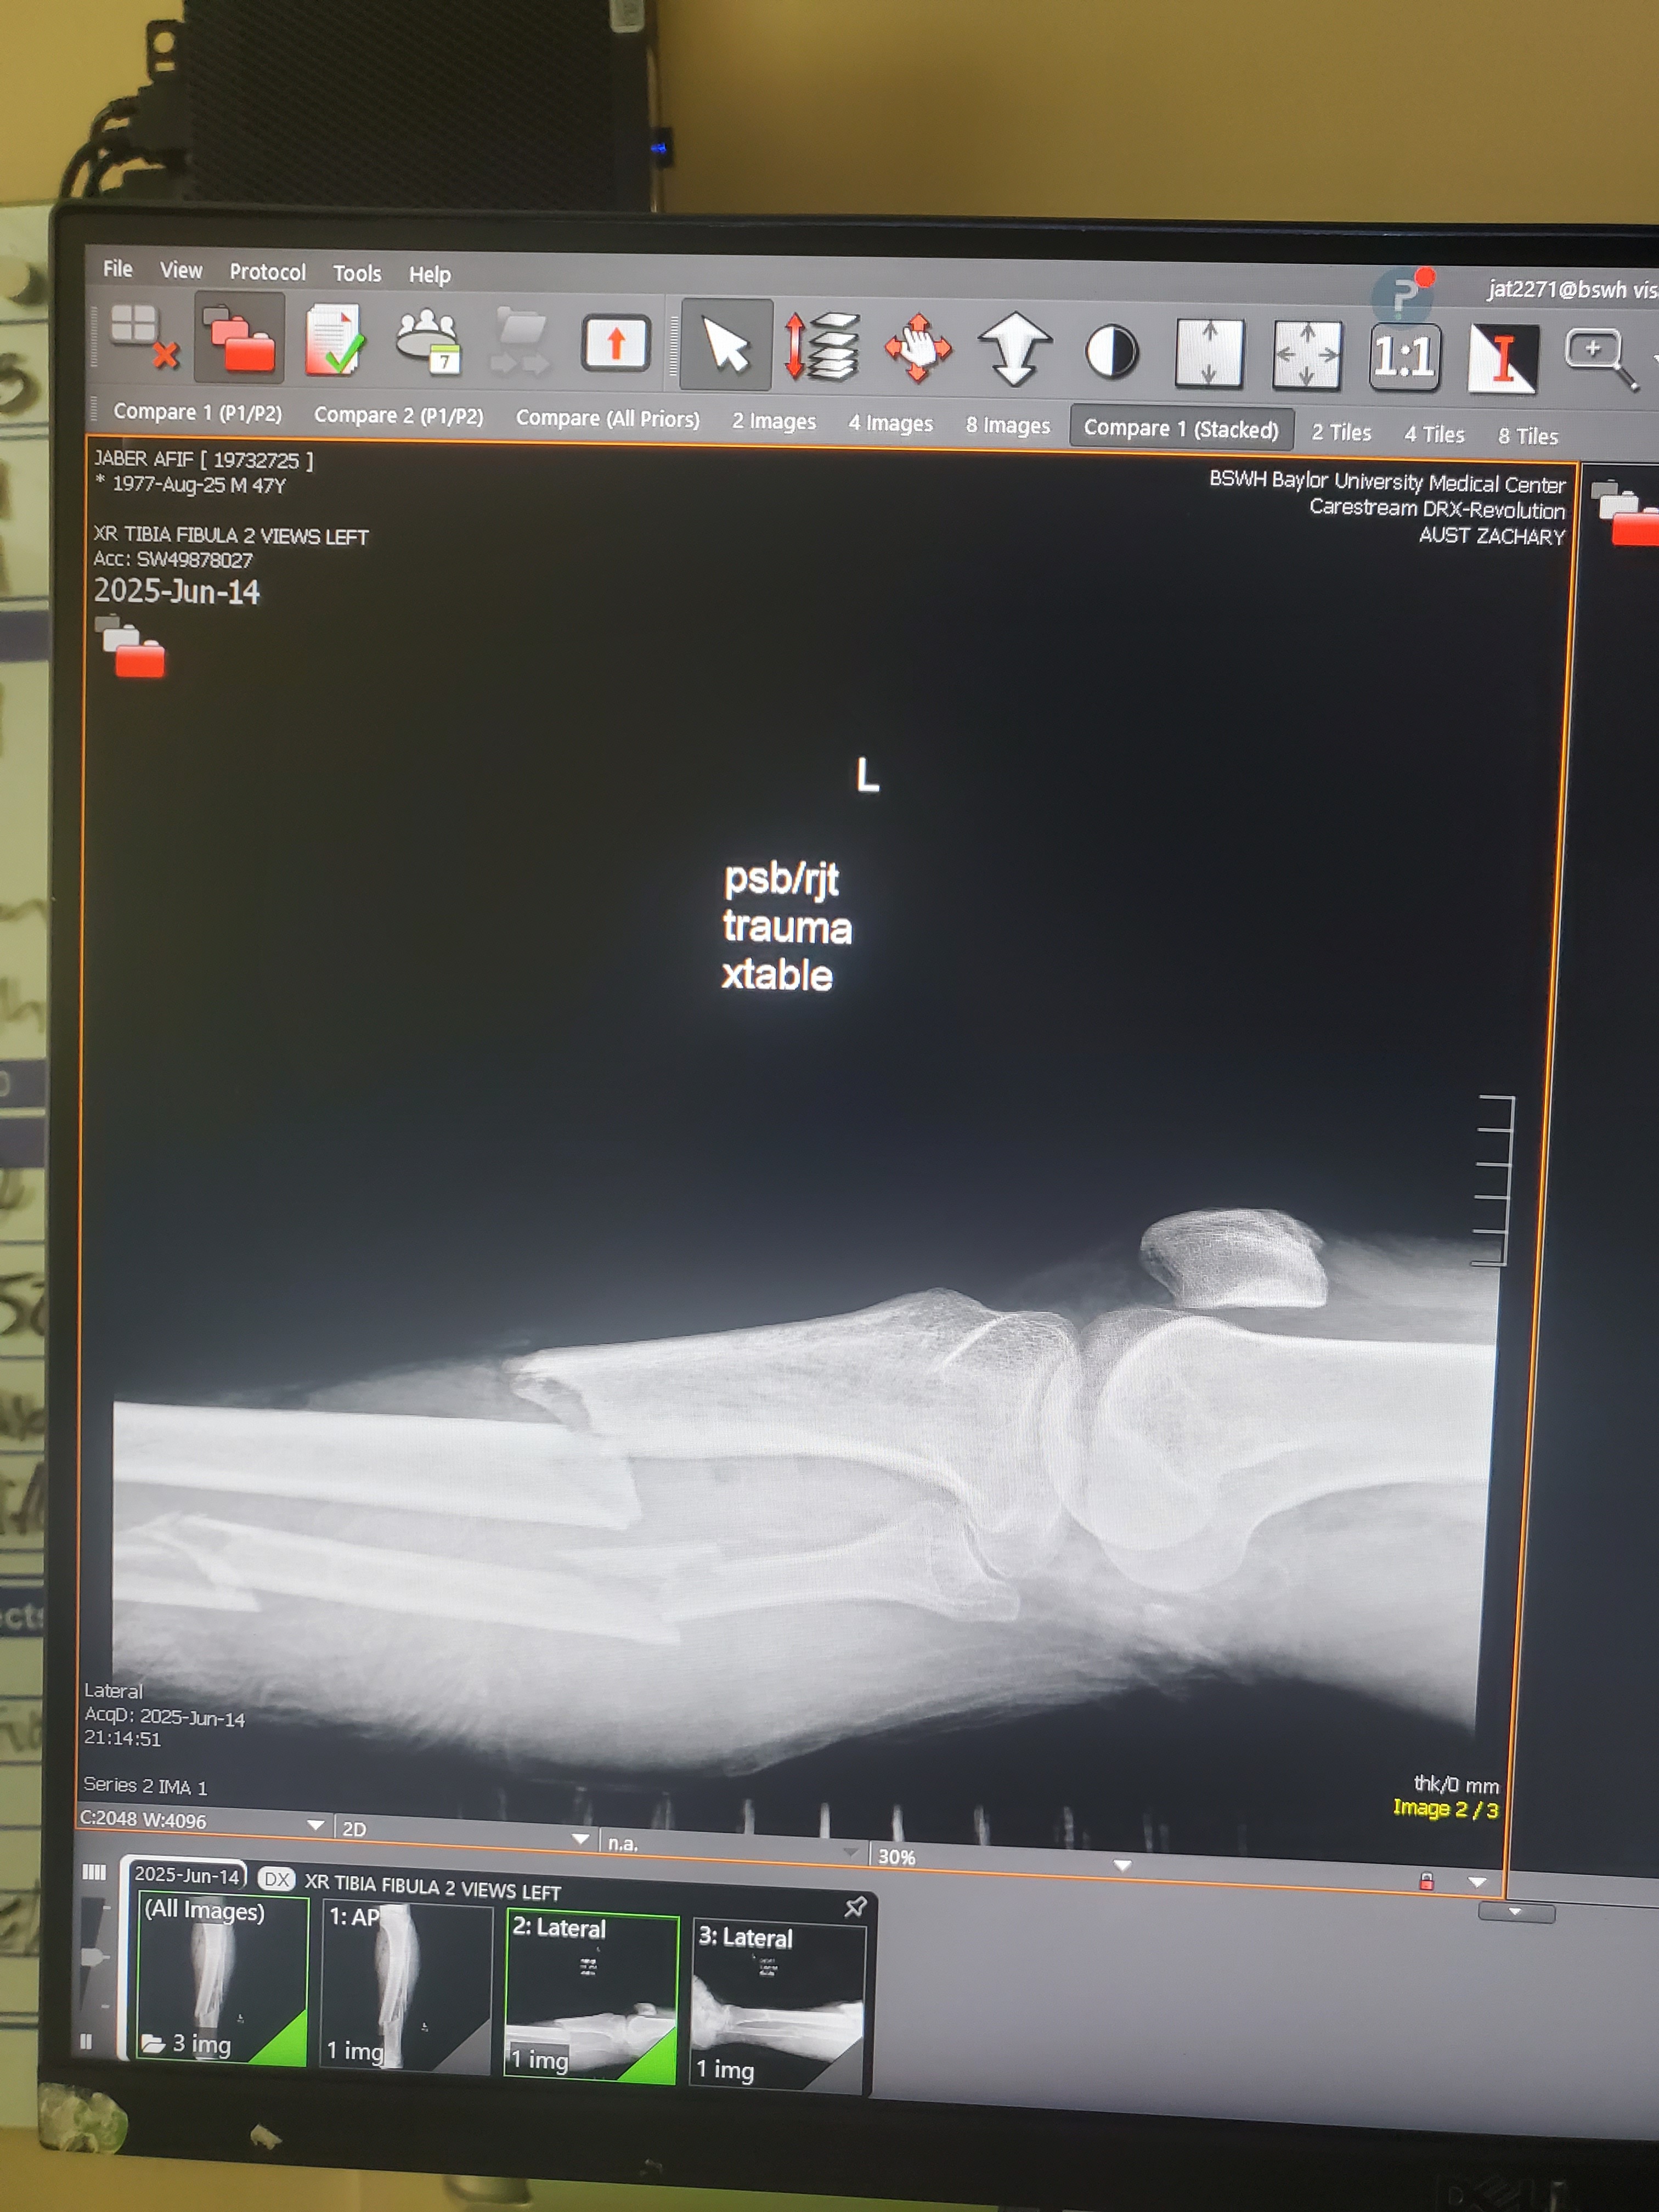

- L

Good afternoon, my name is Afif Jaber, but I'm commonly known as AJ, and I come seeking assistance in this time of an unexpected health emergency stemming from an almost tragic accident on 6/14/25, during which time I had my left leg broken in multiple sections. This accident has unfortunately brought an immense and sudden pileup of medical bills and financial hardship as I'm currentlyunableto work as I heal and look forward to going into therapy. I'd appreciate any and all assistance that I can get as blessed upon your abilities to give towards this urgent request for help and thanking each and everyone in advance for your kind donation. I also accept donations through my CashApp handle $AJHustle77. God bless.